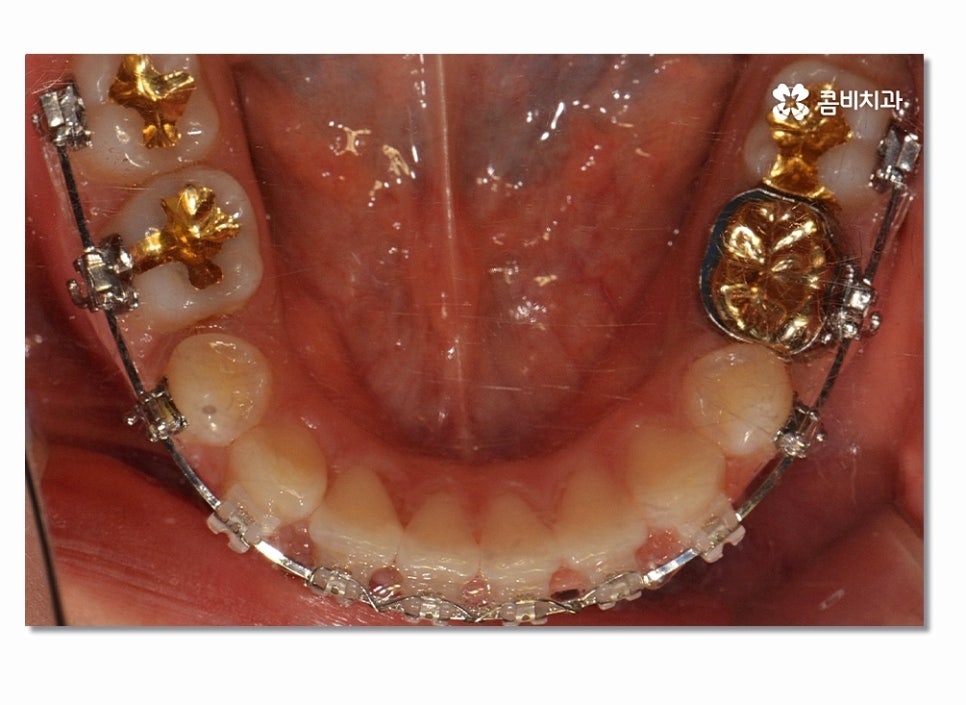

돌출입을 개선하기 위해서는 기본적으로 앞니의 각도와 배열, 위치 등의

조절이 필요하며 발치를 해야 하는 경우 보편적으로 송곳니 옆

작은 어금니를 발치하여 치아의 이동 공간을 확보하는 경우가 많다고 할 수 있어요.

치아교정을 위해서는 치아가 이동할 수 있는 공간이 충분히 확보되어야 하며

돌출입치아교정의 경우 치아가 전방으로 뻐드러진 상태를

후방으로 이동시켜야 하기 때문에 원하는 결과를 위해서 필요에 의해

발치가 진행되는 경우도 많다고 볼 수 있어요.

일반적으로 작은 어금니를 발치하게 되는 이유라면 전체적인

악궁 크기에 맞게 치아를 이동시킬 공간 확보의 의미가 크며